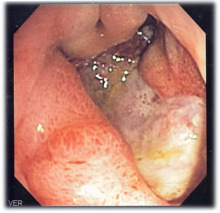

A peptic ulcer may accompany gastritis. Endoscopic image.

Many people with gastritis experience no symptoms at all. However, upper central abdominal pain is the most common symptom; the pain may be dull, vague, burning, aching, gnawing, sore, or sharp.[11] Pain is usually located in the upper central portion of the abdomen,[12] but it may occur anywhere from the upper left portion of the abdomen around to the back.